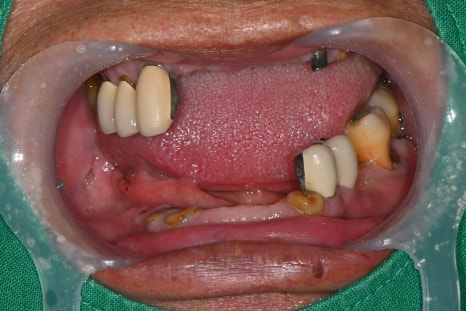

After lower jaw insurance-covered implant placement

After full extraction of the upper teeth one month later